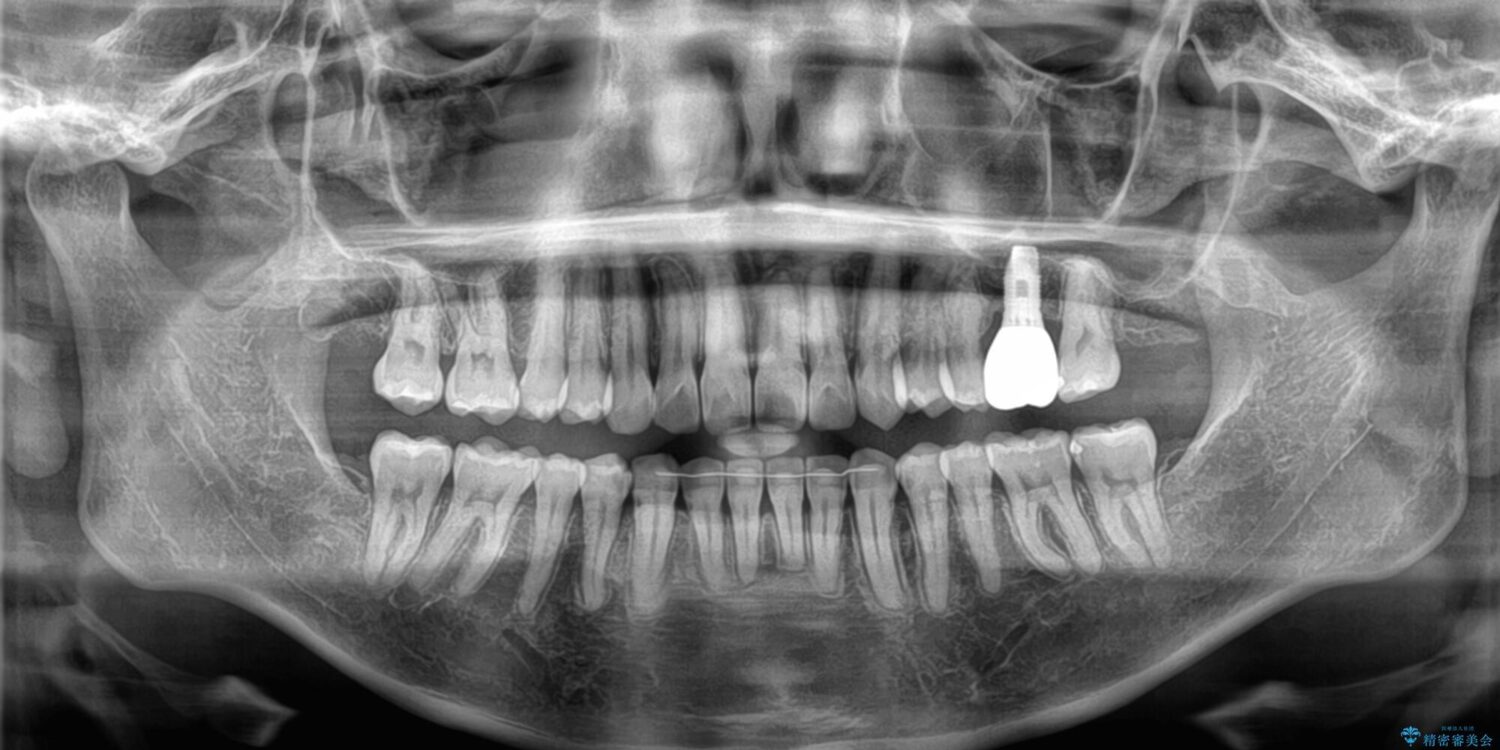

全体的なデコボコと、以前抜歯した歯のスペースを閉じた部分が気になるとのことで来院された患者様です。

左上第一大臼歯を抜歯した際に、スペースを閉じたそうですが、歯が傾斜してものが挟まって不快とのことでした。

インビザライン矯正で全体の歯列と整えるとともに、左上第一大臼歯部にはスペースを作り、インプラントによる補綴治療を行うこととしました。

治療前

• インビザラインによる矯正治療と奥歯のインプラント治療 治療前画像